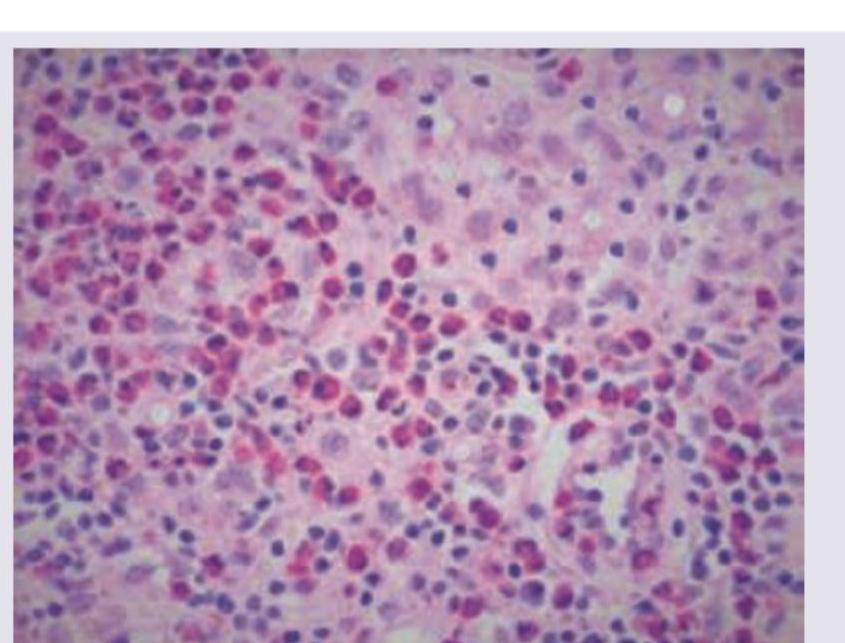

The image shows presence of which cells?

Explanation: ***Langhan cells*** - **Langhan cells** are a type of **giant cell** characterized by multiple nuclei arranged in a **horseshoe or peripheral pattern** [1]. - They are typically found in **granulomas**, especially those associated with **tuberculosis** and other chronic inflammatory conditions [1]. *Epithelioid cells* - **Epithelioid cells** are activated macrophages that resemble epithelial cells and are a key component of **granulomas** [1][2]. - While present in granulomas, they are **mononuclear** and do not have the characteristic multinucleated appearance with peripheral nuclei seen in the image [1]. *Anitschkow cells* - **Anitschkow cells** are plump macrophages with a characteristic **caterpillar nucleus** or **owl-eye appearance**. - They are pathognomonic for **rheumatic fever** and are found in **Aschoff bodies** within the myocardium, not typically in granulomas. *Mott cells* - **Mott cells** are plasma cells containing multiple large, eosinophilic cytoplasmic inclusions called **Russell bodies**. - These inclusions are accumulations of **immunoglobulins** and are seen in conditions with chronic antigenic stimulation, such as **multiple myeloma** or chronic inflammation, but are not giant cells. **References:** [1] Kumar V, Abbas AK, et al.. Robbins and Cotran Pathologic Basis of Disease. 9th ed. Inflammation and Repair, p. 109. [2] Cross SS. Underwood's Pathology: A Clinical Approach. 6th ed. (Basic Pathology) introduces the student to key general principles of pathology, both as a medical science and as a clinical activity with a vital role in patient care. Part 2 (Disease Mechanisms) provides fundamental knowledge about the cellular and molecular processes involved in diseases, providing the rationale for their treatment. Part 3 (Systematic Pathology) deals in detail with specific diseases, with emphasis on the clinically important aspects., pp. 198-200.